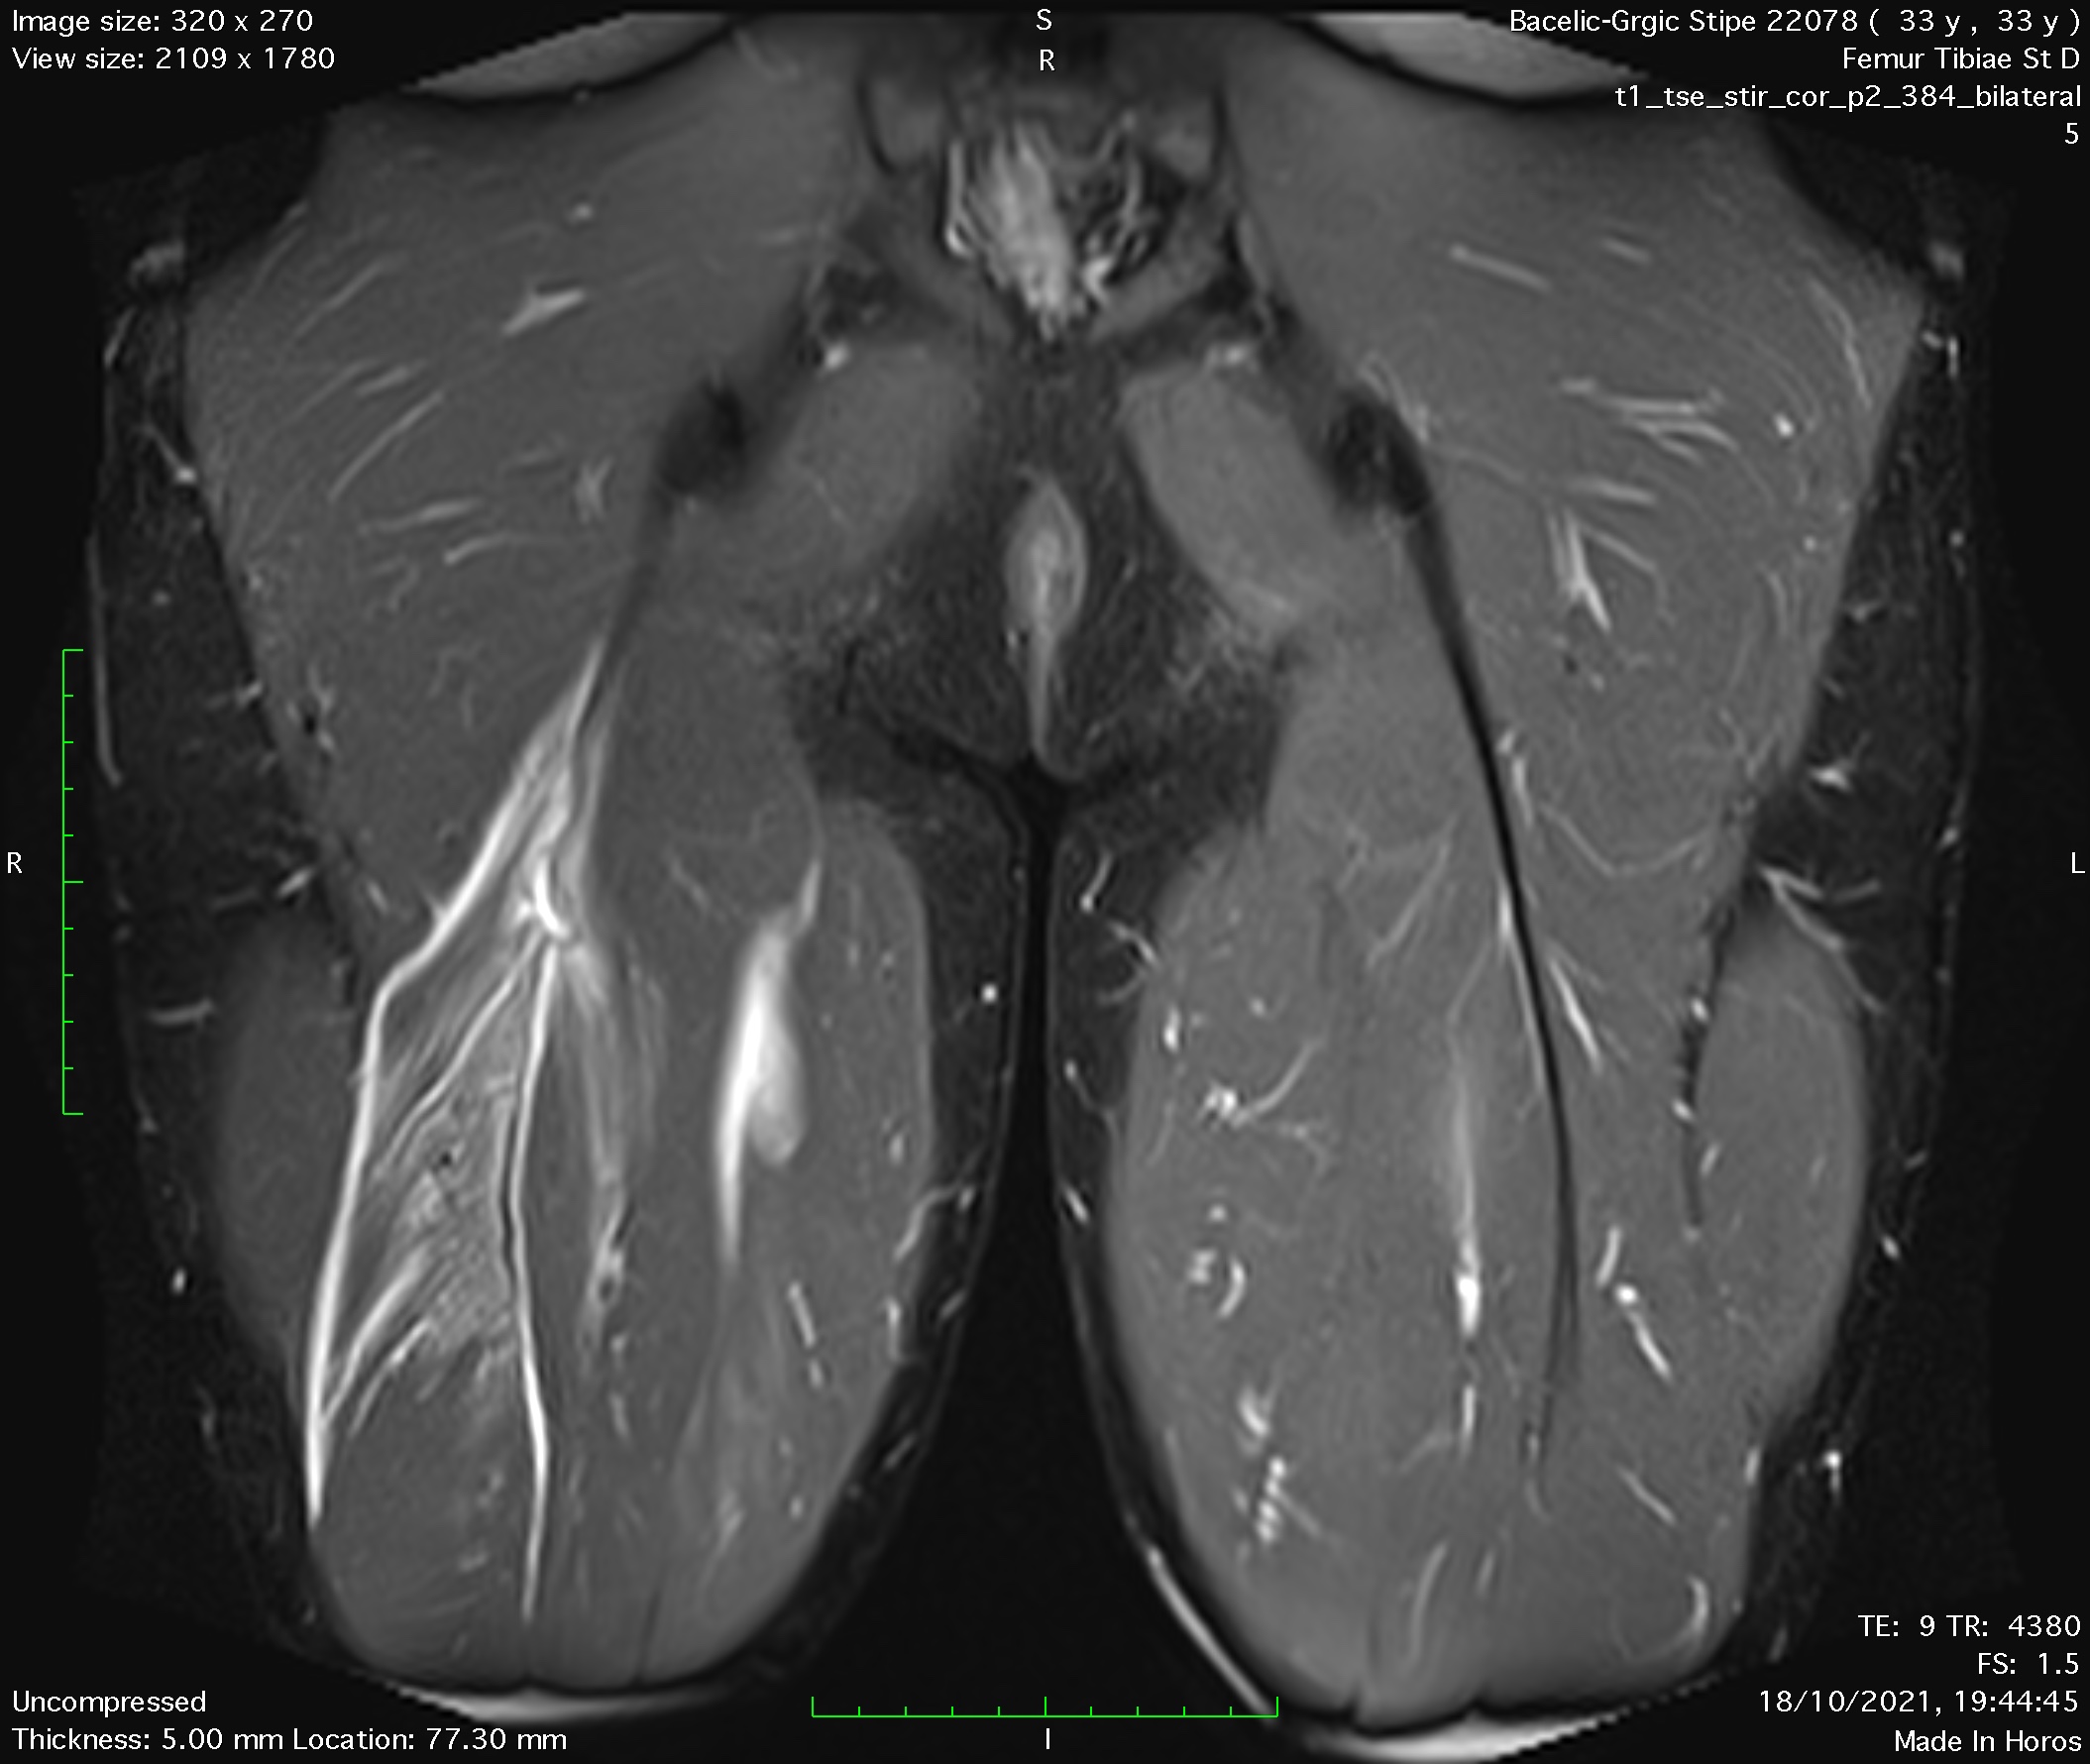

A few days ago, a new case-injury arose. A long-time patient and a dear friend injured himself during a soccer match by trying to play a heel pass. Immediately it was seen that the injury is severe. MRI confirmed expectations, intramuscular hamstring biceps tendon tore. It is a very complicated and long healing injury and usually misdiagnosed as a simple muscle rupture.

MRI of hamstring intramuscular biceps tendon injury